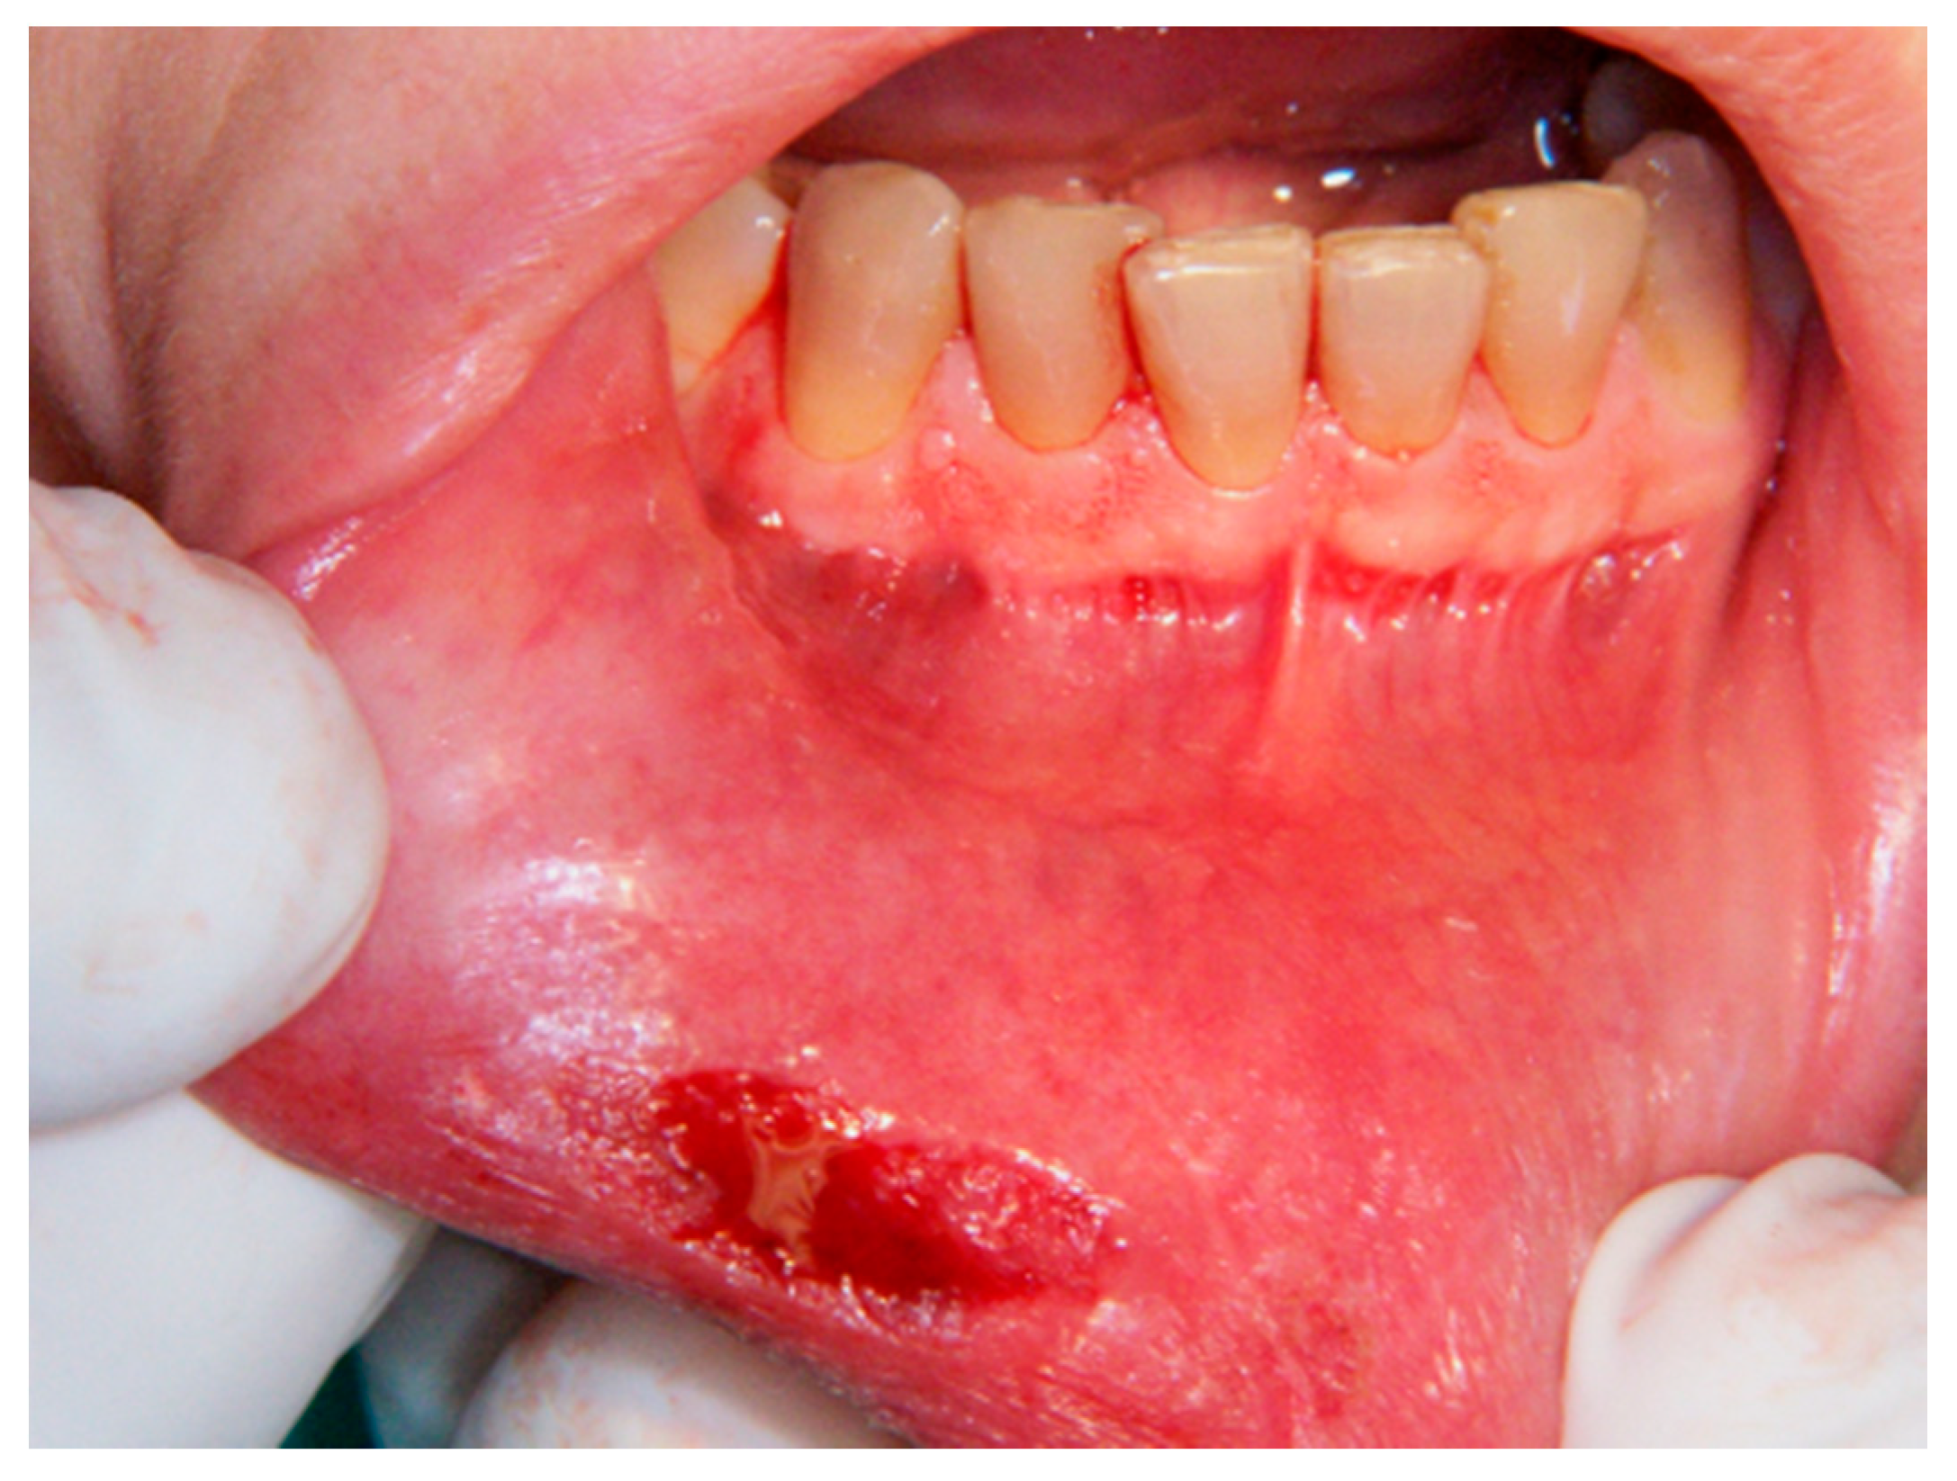

Figure 3.

Bleeding which appeared after lesion excision.

2.3.1. Er,Cr:YSGG Laser

An Er,Cr:YSGG laser with a wavelength of 2790 nm (Waterlase, Biolase Inc., Foothill Ranch, CA, USA) was used. After the injection of local anesthesia, the excision areal limit was delimited by the laser beam without air–water spray with an output power of 0.25 W and 20 Hz (Figure 1, Figure 2 and Figure 3). An excision was made for all lesions with an output power of 1.5 to 2 W (27 J/cm2), a fiber diameter of 600 μm, and pulsed mode (20 Hz, 60 μs). In addition, a defocused (noncontact) mode without air–water spray was used for the coagulation of the bottom of the wound at the end of the excision to ensure a primary coagulation. The wound was left to heal in the second intention, and no sutures were made.